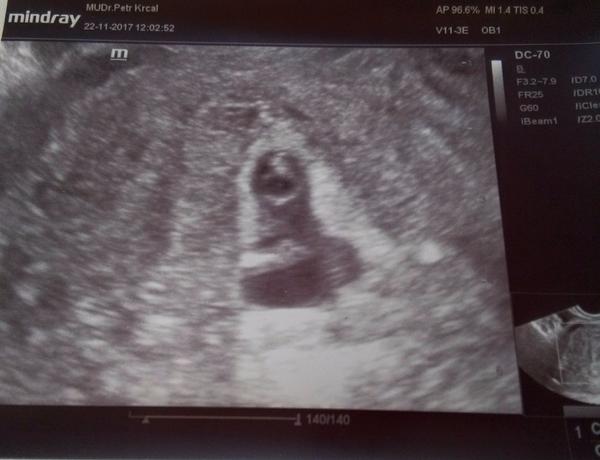

@ms.neomagic moc děkuju 🙂 no dnes jdu na další UTZ, chodím po týdnu, dr.si mě chce ohlídat když jsem měla 2x ZT . Tak snad už ted do třetice bude vše v pořádku. 🙏 snažím se být v pohodě, ale ten strach vždycky když jdu na kontrolu tam je.

@laura7279 Teda tak tu jen tak pokukuju a najednou koukám co to máš dole,a on krásný 7tt..opravduuu? A vše v pořádku? Moc moc gratuluju a držím všechno co mám <3 <3 <3